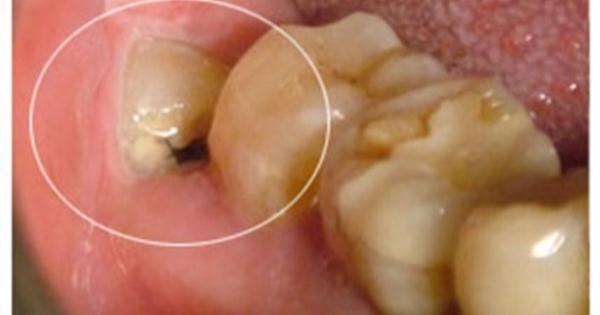

在平時,細菌造成的慢性感染會使牙齦發炎,容易流血,出現骨吸收、蛀牙及牙痛,最後因牙周病的牙齒鬆動或牙髓壞死而拔牙。這時隔壁有用的第二大臼齒 往往 也會受到波及而造成不等程度的傷害,甚至拔牙,這也是最可惜的地方。在身體疲累虛弱或重病時,細菌引起的急性發炎反應更是厲害,輕者造成智齒周邊紅熱腫 脹,疼痛不堪,張口、吞咽、咀嚼困難及淋巴腺腫等等;重者引起大範圍感染,導致腫脹的蜂窩織炎,化膿性腫脹及發燒惡寒等全身性癥狀,如未予以適當處置(抗 生素及切開引流手術),甚至會有致命危險。

此外智齒若長不出來,殘餘的牙胚有可能會變性而形成口腔腫瘤。空間不足時其牙胚可能會吸收前方第二 大臼齒之牙根使其強度減低,影響其功能。異位或萌出不全的智齒亦往往會對正常咬合造成幹擾,牽動下頜骨之肌肉必須常常做出異常收縮來避開此幹擾,而使得肌 肉及關節容易有發炎疼痛之現象。

2.經常並發急、慢性冠周炎的低位垂直阻生智齒,已成影響身體健康的病灶牙,應予拔除。

3.近中傾斜阻生智齒,雖暫無癥狀,但該智齒的存在可造成第二磨牙的遠中鄰面牙頸部齲洞。為了保護有重要咀嚼功能的第二磨牙,主張早期拔除此類阻生智齒。

5.智齒牙位雖正常,但智齒牙冠有骨組織或牙齦瓣覆蓋,經常發生冠周軟組織發炎、腫脹、疼痛者

6.智齒已齲壞,或發生牙髓炎,又不便進行牙體牙髓治療者